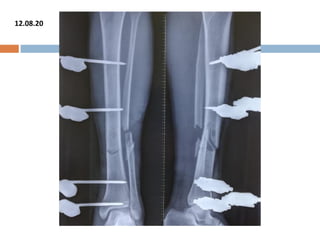

12.08.20

FOLLOW UP